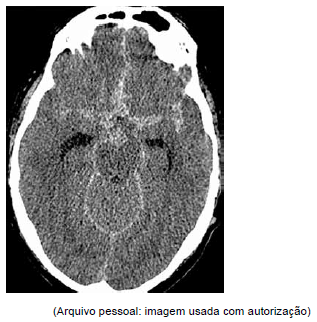

Mulher de 46 anos apresenta quadro agudo de cefaleia intensa que a interrompeu no meio da frase e foi seguida imediatamente por náuseas e vômitos. A tomografia computadorizada realizada é mostrada a seguir.

O diagnóstico mais provável é: